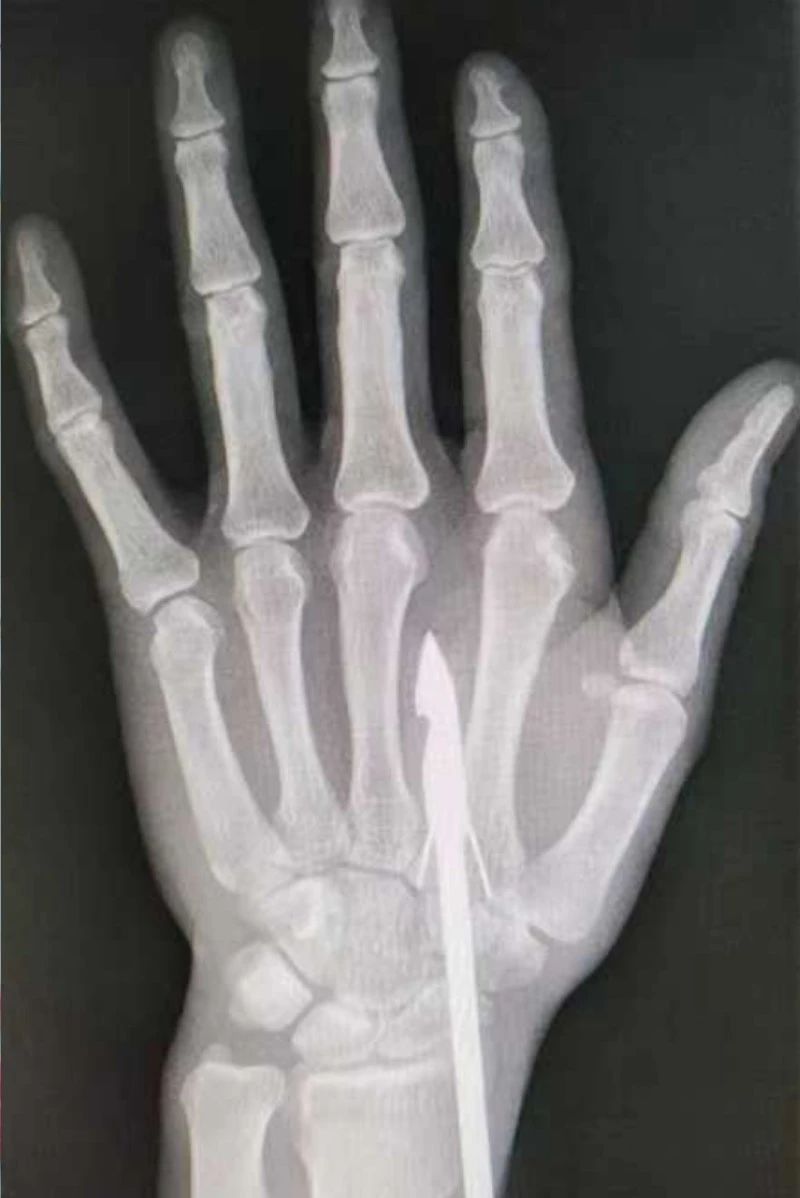

時間緊迫,每一秒的流逝都可能對傷者的手部功能造成不可逆的損害。接診醫(yī)生代彭威,迅速對傷者進行了初步檢查。他注意到,魚鉤已經(jīng)深深嵌入皮膚,情況遠比表面看起來復(fù)雜。沒有絲毫猶豫,立即安排了X線檢查以確認(rèn)魚鉤的位置及傷及范圍,以及急診化驗檢查以評估患者的整體狀況。

確保在取出魚鉤的同時,不對周圍的組織造成額外的傷害。8點15分左右患者在局部浸潤麻下進行手術(shù),經(jīng)探查后魚鉤未傷及重要血管、神經(jīng)及肌腱,經(jīng)過緊張的十分鐘,魚鉤終于被順利取出,隨后對傷口進行了仔細(xì)的清理和縫合,用敷料仔細(xì)包扎,確保傷口能夠順利愈合。